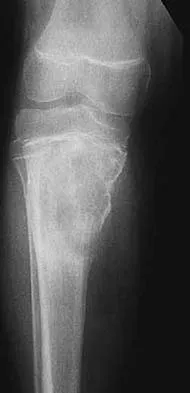

Practice Orthopedics online MCQs and assess your clinical knowledge. High-yield questions for medical students and orthopedic residents.